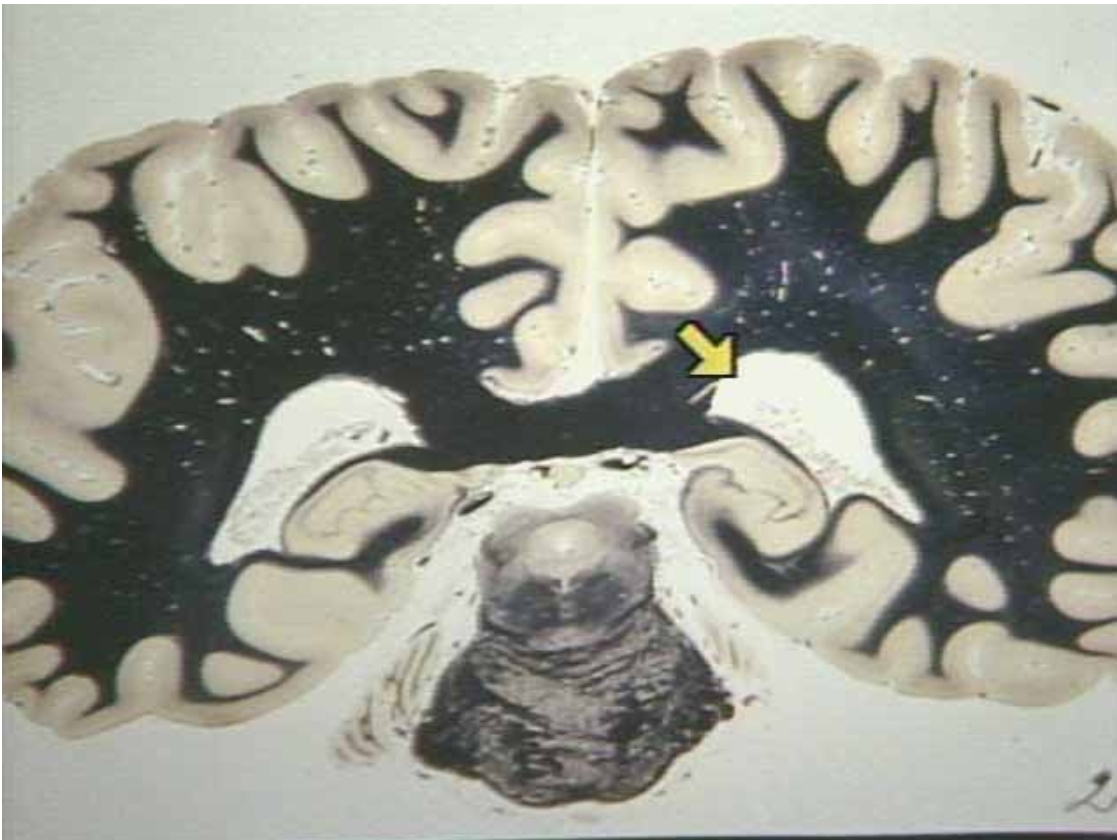

What is the arrow pointing at?

Hippocampus